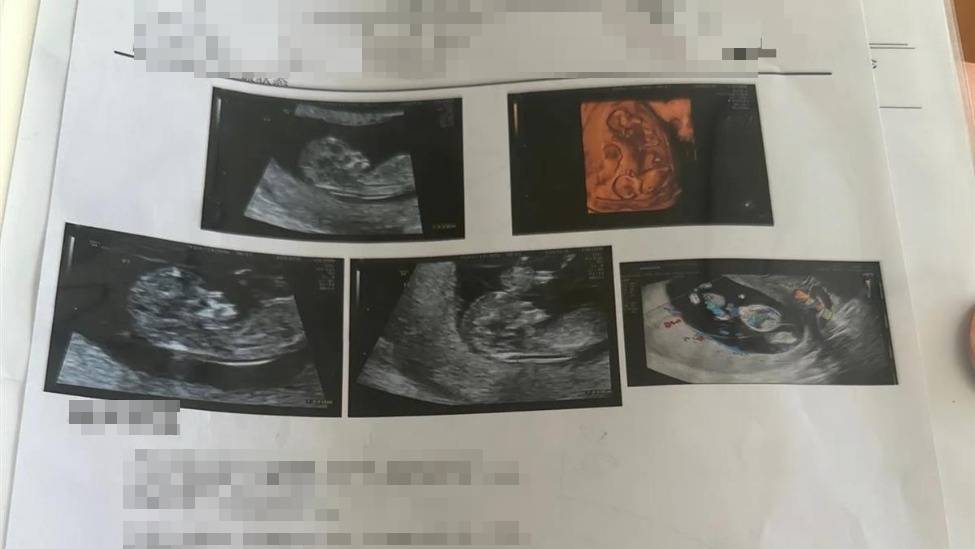

Mới đây, cô Wang đến từ Phúc Thuận, tỉnh Liêu Ninh, Trung Quốc, đã đăng tải trên mạng xã hội rằng cô đang mang thai 16 tuần. Từ tháng 11 đến tháng 12/2025, cô đã trải qua 4 lần khám thai tại bệnh viện và mỗi lần siêu âm đều cho thấy có thêm một thai nhi, dẫn đến việc mang thai 4.

Đi khám thai, người phụ nữ sốc nặng sau khi siêu âm - Ảnh 1.

Mỗi lần siêu âm người phụ nữ đều cho thấy có thêm một thai nhi, dẫn đến việc mang thai 4.

Theo lời Wang, cô 30 tuổi và mang thai tự nhiên vào tháng 9/2025. Wang đã đi khám thai 3 lần tại Bệnh viện Sản Nhi Phúc Thuận vào tháng 11/2025. Lần khám đầu tiên cho thấy cô mang thai đơn, lần thứ 2 cho thấy mang thai đôi và lần thứ 3 cho thấy mang thai ba. Để làm rõ tình hình, Wang đã đến Bệnh viện Sản Nhi Thẩm Dương để khám lại vào tháng 12/2025 và kết quả siêu âm cho thấy cô mang thai 4.

Theo kết quả siêu âm thai lần thứ 4 của Wang, thai nhi thứ 4 của cô được phát hiện là không có tim. Bác sĩ giải thích rằng mặc dù thai nhi thứ 4 của cô không có tim thai nhưng mạch máu lại nối với 3 thai nhi còn lại, được các thai nhi khác cung cấp máu. Nếu cả 4 thai nhi cùng trứng phát triển bình thường, có thể dẫn đến các thai nhi khác có triệu chứng suy tim bẩm sinh.